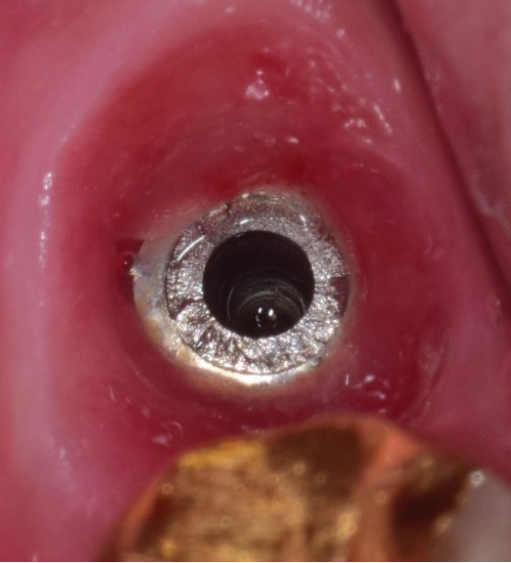

1) 보철물연결나사 제거

임플란트연결나사는 보통 30N으로 채결되어 구강내에서 오랜기간을 유지하게 되는데 사용기간동안 반복되는 진동으로 풀리는 경우가 생길 수 있다. 이런 경우에는 보촐물의 동요도를 인지하게 되는데 서둘러서 치과를 방문하여 다시 조여주면 큰 문제가 없지만 방치하게 되면 피로파절이 발생하게 된다. 이때는 일단 먼저 보철물을 먼저 제거하고 파절된 나사를 제거하면 된다. 연결나사는 초음파기구로 역회전을 주면서 돌리면 조금씩 밀려나오게 되는데(Fig. 3) 이때 곧게 핀 익스플로러를 이용할 수도 있다(Fig. 4).